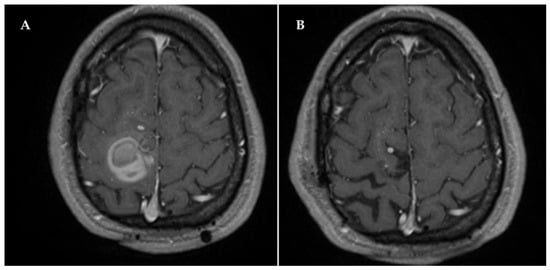

2. Case Description